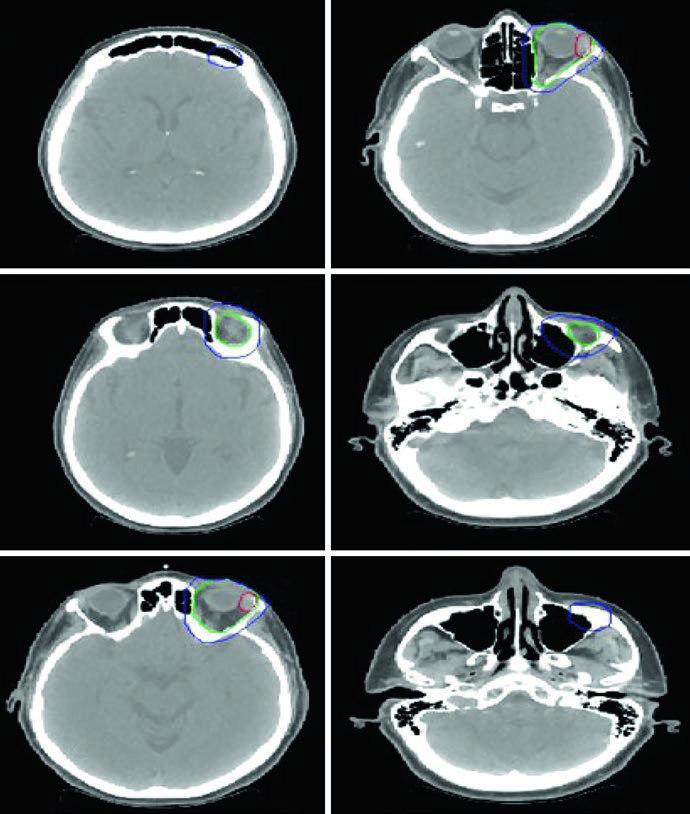

DLBCL de Cabeça e Pescoço

Uma mulher de 47 anos com DLBCL estádio IIA de tonsila esquerda e pescoço esquerdo (nível 2, 5,6 cm) recebeu 3 ciclos de R-CHOP seguidos de RT consolidativa. Simulada com pescoço em extensão, imobilizada com máscara aquaplast de 5 pontos. O CTV ISRT cobre toda a tonsila esquerda e o nível ganglionar envolvido, incluindo 1–2 cm superior e inferior à extensão pré-quimioterapia. Casos de linfoma de cabeça e pescoço exigem atenção especial ao registro entre PET diagnóstico e CT de simulação.

Linfoma Orbital e Sinonasal

A simulação é feita em decúbito dorsal, braços ao lado do corpo e imobilização com máscara termoplástica. Para linfoma orbital, as opções técnicas incluem par de cunhas superior-inferior, 3DCRT ou IMRT. Bolus pode aumentar a dose superficial em doença localizada de tecidos moles. Quando a dose prescrita alcança 30 Gy ou mais, considerar blindagem da glândula lacrimal.

Em doença indolente limitada da conjuntiva, o tratamento com feixe de elétrons anterior ou energia mista elétrons/fótons é uma alternativa, com blindagem do cristalino se o tumor estiver na periferia. Para linfomas sinonasais, 3DCRT ou IMRT é recomendada pelas doses mais altas necessárias e pela proximidade de estruturas críticas.

O caso ilustrativo é uma mulher de 56 anos com DLBCL de seio etmoide/esfenoide esquerdo, com extensão para a cavidade nasal direita cruzando o septo, erosão da placa cribriforme superiormente, erosão da parede orbital medial esquerda lateralmente e extensão para o seio maxilar esquerdo inferiormente. O seio frontal esquerdo estava completamente opacificado. Após ressecção quase total e 3 ciclos de R-CHOP, a RT consolidativa foi administrada com CTV ISRT cobrindo a totalidade dos seios envolvidos. A abordagem de delineamento de tumores da cavidade nasal e seios paranasais segue princípios semelhantes.